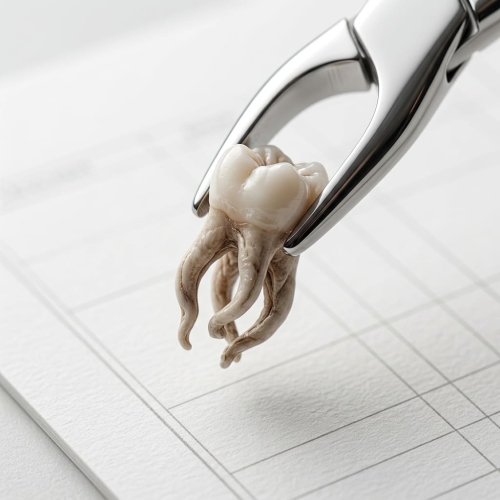

„Chiar trebuie să tratez din nou, dacă părea că totul s-a făcut deja?” – această întrebare apare frecvent în mintea pacienților care au trecut printr-un tratament radicular necorespunzător. Canalele dentare complexe, fisurile și orificiile ascunse devin adesea refugiu pentru bacterii, iar salvarea dintelui depinde de microscop și de precizia medicului.

Primele 30 de minute după ce un copil scoate un dinte permanent sunt cruciale - în această perioadă se decide dacă dintele poate fi salvat și dacă se poate evita un tratament complex. Voi explica ce trebuie făcut cu un astfel de dinte înainte de a ajunge la clinica stomatologică, pentru a maximiza șansele de recuperare cu succes.